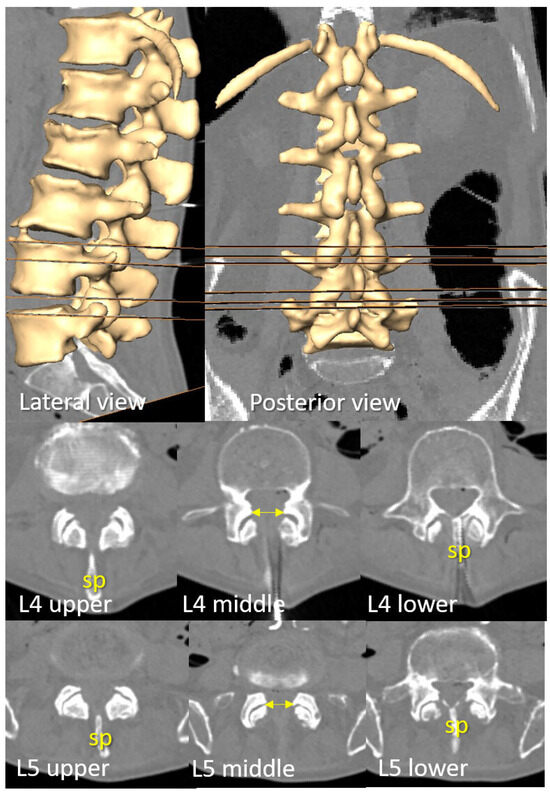

Open AccessArticle

by

Anna Puigdellívol-Sánchez, Hipólito Labandeyra, Alberto Prats-Galino and Xavier Sala-Blanch

NeuroSci 2025, 6(4), 119; https://doi.org/10.3390/neurosci6040119 - 21 Nov 2025

Background: The skin-to-transverse process distance (st) correlates with the skin-to-dural sac depth (d) and may be used to estimate optimal angles for perpendicular needle insertion using the formula inverse cosine d/√(1 + d2), as outlined in free visual guides. Objective: We

Background: The skin-to-transverse process distance (st) correlates with the skin-to-dural sac depth (d) and may be used to estimate optimal angles for perpendicular needle insertion using the formula inverse cosine d/√(1 + d2), as outlined in free visual guides. Objective: We aimed to analyze the relationship between the transverse process and dural sac depth at lumbar levels relevant to spinal anesthesia and to determine the range of planes where perpendicular paramedian needle insertion is feasible when midline access is not viable. Methods: Ten ex vivo trunks were flexed using an abdominal support, and CT scans were performed. Correlations between the transverse process and dural sac depth were evaluated from L3 to S1. Perpendicular planes at the level of needle paths were examined at L3–L4 and L4–L5. Median path viability was assessed. Results: The transverse process aligned with the dorsal dural sac at L3, the posterior third at L4, and the middle zone at L5 or S1. Median needle insertion was not viable in 20–30% of L4–L5 and L3–L4 levels, respectively. However, paramedian access was possible. The vertical range of viable paramedian planes was 8.7 ± 2.9 mm (L4–L5) and 7.9 ± 1.9 mm (L3–L4). Coronal reconstructions showed that the upper level of the transverse process correlates with the skin-perpendicular planes where insertion is likely to succeed. Conclusion: Many elderly spines lack viable midline paths. The superior aspect of the transverse process serves as a useful landmark for estimating dural sac depth, calculating paramedian angles, and identifying the plane for successful perpendicular needle insertion.

Figure 1